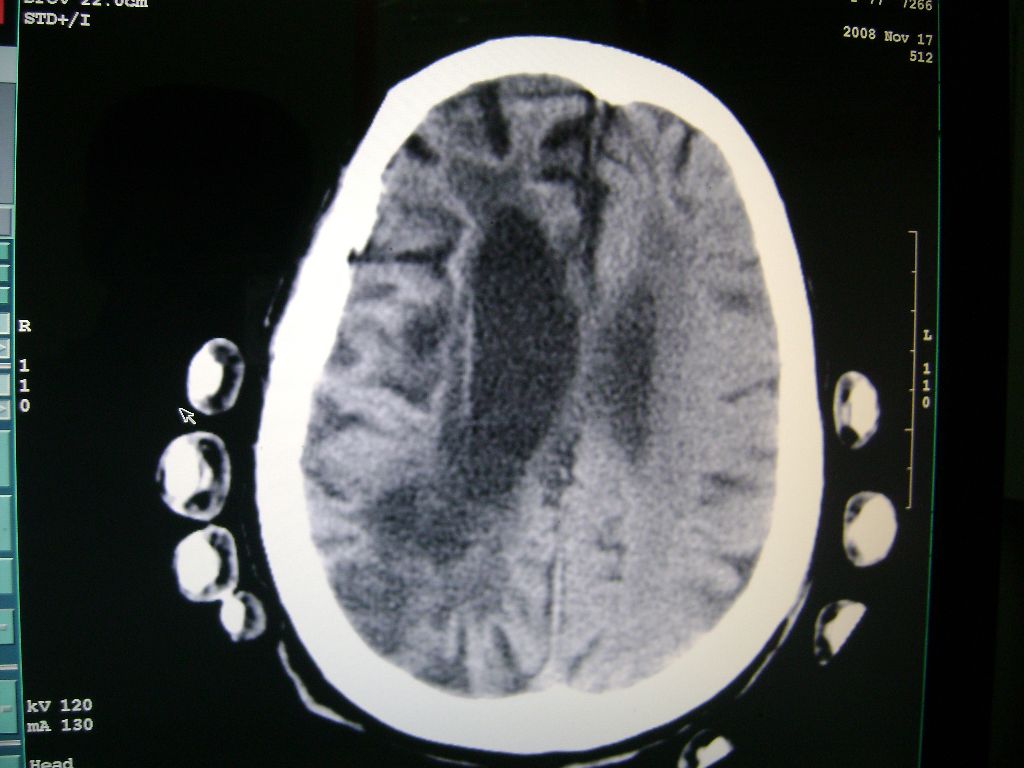

标题: CT16663:F 77 昏迷不醒,各位老师看咯! [打印本页]

f 77 昏迷不醒

右侧额颞枕顶叶脑软化灶,脑萎缩,大脑中动脉壁钙化。

右侧半球陈旧性卒中,不除外伴有新病灶,左额叶梗塞,双侧大脑中动脉钙斑

右侧额颞枕顶叶脑软化灶,脑萎缩,大脑中动脉壁钙化。不支持出血(密度高,边界清且局限)顶枕区似有新发梗塞,建议核磁

1)右侧额颞枕顶叶脑软化灶;其内高密度影,多为钙化灶。2)脑萎缩。3)大脑中动脉钙化。

右侧陈旧脑梗塞伴脑萎缩。脑内点状钙化。大脑中动脉壁钙化灶。无出血灶。

1)右侧额颞枕顶叶脑软化灶并钙化灶可能。2)脑萎缩。3)大脑中动脉钙化。 -